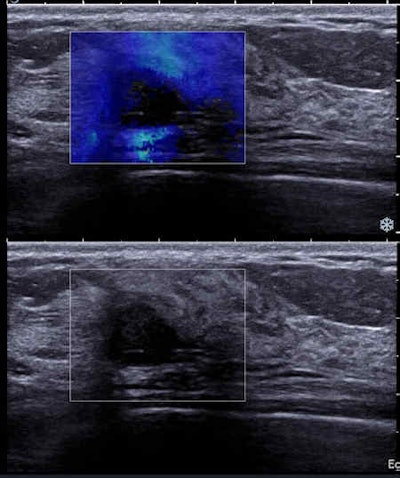

A 33-year-old woman with 15-mm palpable lump in right breast. Top: Mammogram (mediolateral oblique view) shows an oval-shaped mass with indistinct margins. Bottom: Sonogram with shear-wave elastography shows a round mass with hypoechogenicity, abrupt interface, posterior acoustic enhancement, and a low color rating. All the benign criteria (oval mass, circumscribed margin, etc.) are not filled for fibroadenoma. This is categorized as BI-RADS 4. Biopsy under ultrasound guidance: grade III triple-negative (TN) ductal invasive carcinoma (estrogen-negative, progesterone-negative, HER2-negative cancer). TN cancers may have pseudobenign imaging features and be classified BI-RADS 3.